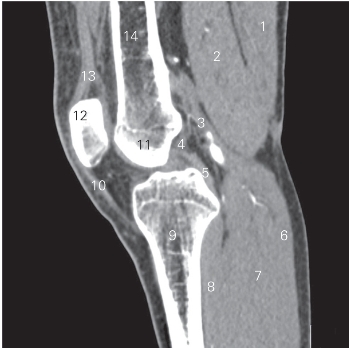

图5-21 经前后交叉韧带的矢状断层CT 图像(软组织窗)

1 半腱肌 semitendinosus 2 半膜肌 semimembranosus

3 腓肠肌内侧头 medial head of gastrocnemius

4 前交叉韧带 anterior cruciate ligament

5 后交叉韧带 posterior cruciate ligament

6 腓肠肌 gastrocnemius 7 比目鱼肌 soleus

8 腘肌 popliteus 9 胫骨 tibia

10 髌韧带 patellar ligament

11 股骨外侧髁 lateral condyle of femur 12 髌骨 patella

13 股四头肌肌腱 tendon of quadriceps femoris

14 股骨 femur